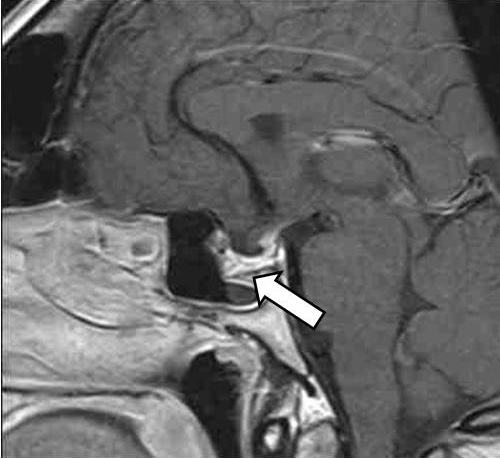

Клиническое наблюдение

Женщина 42 лет 09.12.2020 была доставлена бригадой скорой медицинской помощи с подозрением на острое нарушение мозгового кровообращения в приемное отделение БУЗ УР «1 РКБ МЗ УР» с жалобами на сильную головную боль в лобной области, повышение артериального давления (АД) до 160/100 мм рт. ст., общую слабость, повышение температуры тела до 37,5 °C, по поводу чего принимала метамизол натрия без эффекта. По результатам компьютерной томографии головного мозга данных за острое нарушение мозгового кровообращения выявлено не было; обнаружена макроаденома гипофиза размерами 28 × 21 × 22 мм с интра-, инфраселлярным ростом, распространявшаяся из гипофизарной ямки через разрушенное дно турецкого седла в полость основной пазухи. По данным далее проведенной магнитно-резонансной томографии (МРТ) гипофиза с контрастированием подтверждена макроаденома гипофиза размерами 22 × 32 × 23 мм с супра-, инфра-, латероселлярным ростом с компрессией воронки гипофиза, хиазмы зрительных нервов слева, охватом внутренней сонной артерии с двух сторон (рис. 1). Гормональное исследование от 12.01.2021: ИФР-1 – 49,8 нг/мл (43–209)1 [1]. При компьютерной сферопериметрии выявлены единичные периферические относительные скотомы, абсолютные скотомы правого глаза и рассеянные относительные скотомы левого глаза.

Рис. 1. Магнитно-резонансная томография гипофиза с контрастным усилением, Т1-взвешенные изображения. Визуализируется макроаденома гипофиза с супра-, инфра-, латероселлярным ростом с кровоизлиянием (указана стрелкой)